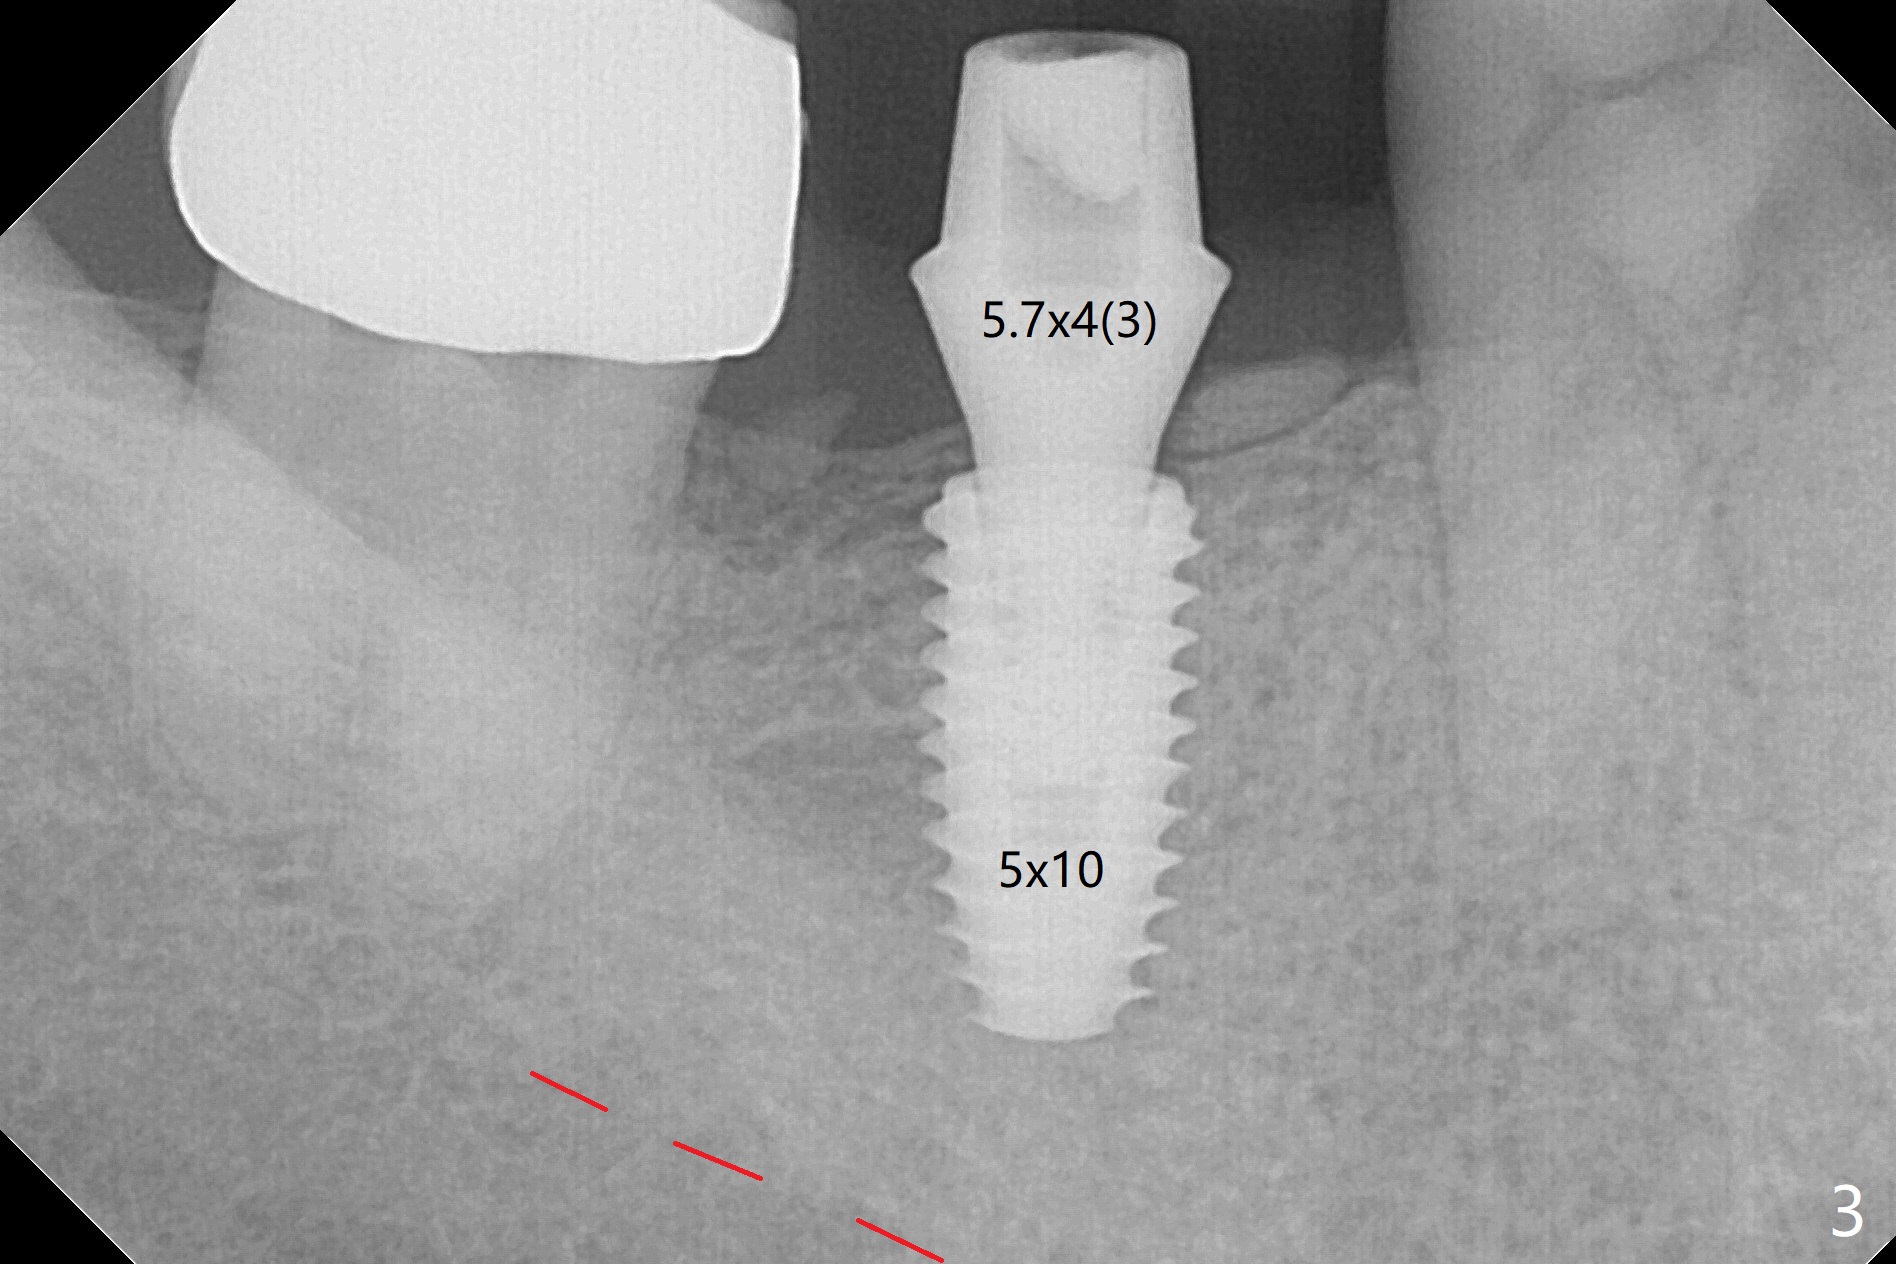

The edentulous ridge at #31 is anesthetized with one carpule of Lidocaine in an infiltration manner for guided surgery (Fig.1,2). In comparison, two or 3 carpules of Lidocaine are required for anesthesia for delayed implant placement without guide. It suggests that guided surgery is associated with less pain. Besides, the implant placed with guide has good trajectory and depth in a timely manner (Fig.3). Since the patient is a heavy bruxer with dislodgement of #30 provisional and #19 abutment screw loosening, a 5.7x4(3) mm cementation abutment is placed immediately so that a splinted provisional is fabricated for #30 and 31 for better retention. However, the gingiva around the implant at #31 is unhealthy 3 months postop (Fig.4). After impression, the provisional at #31 is sectioned without recementation for better oral hygiene. The distal gingival embrasure is large, associated with food impaction (Fig.5). Two years post cementation, the proximal contacts are trimmed (Fig.6 *) for pick up impression for crown repair. The implant and abutment contact is clearly shown with change in X-ray projection (Fig.7). When the new crown with flattened proximal contacts is being seated, it is tight mainly distal. After distal proximal contact adjustment, the crown is recemented without taking out crown/abutment for residual cement removal, because they may be unable to be completely seated because of the flattened larger proximal contacts (hand torque before impression).